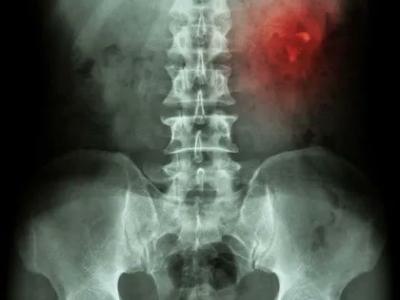

FDG-PET Scan in RA? Study of 34 #RA pts shows PET uptake (SUV scores) measures were significantly correlated with the nu

FDG-PET Scan in RA? Study of 34 #RA pts shows PET uptake (SUV scores) measures were significantly correlated with the number of swollen joints, SDAID but not the CDAI, disease duration, seropositivity, or RA treatments. https://t.co/AkGhEiNqwt https://t.co/FkKh49KYyd